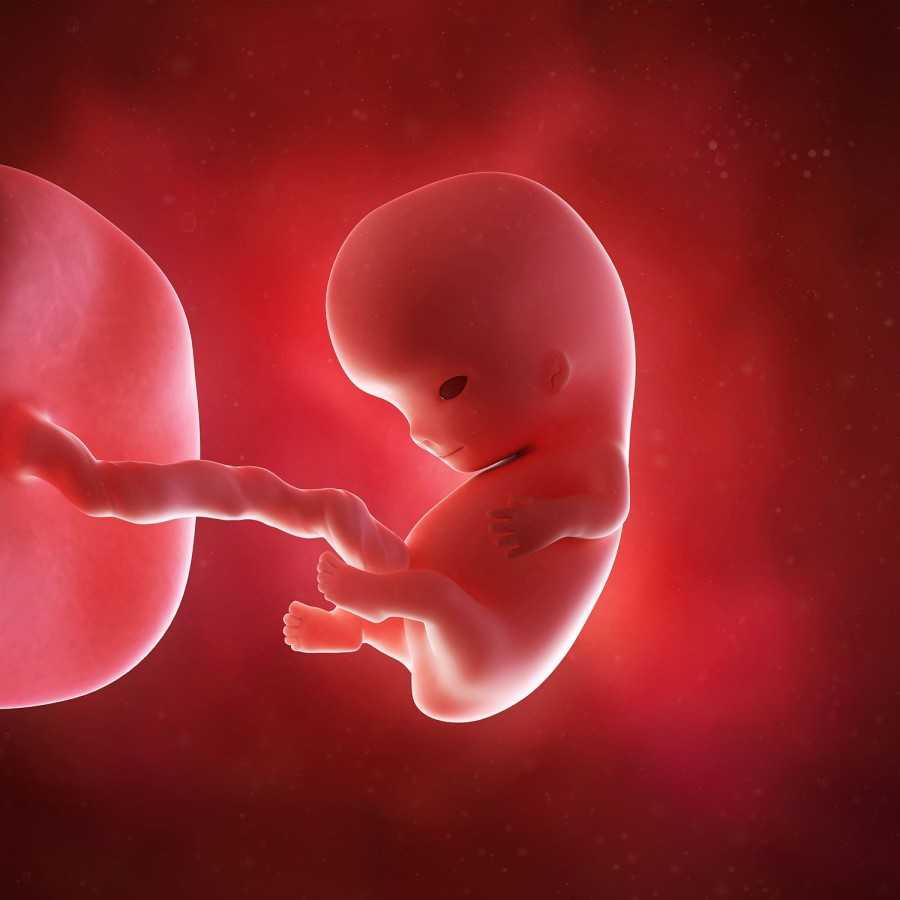

Стадии развития эмбриона

Ребенок в животе по неделям